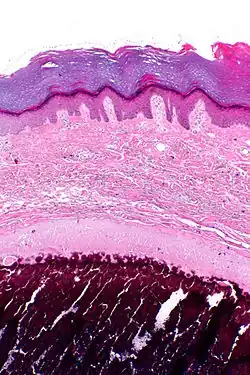

![]() | |

| Micrograph of calcinosis cutis. The calcification is purple (bottom of image). H&E stain. | |